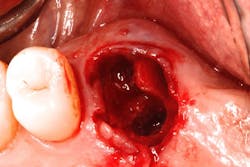

The authors noted a paradigm shift in their practices over the last several years. Hattingh et al. published a technique article regarding immediate placement of ultrawide diameter implants in molar sockets.14 Instead of the more traditional protocol that involved diagnosis of a nonrestorable molar with subsequent extraction, graft, osseous healing, implant placement, osseointegration, and implant restoration, the authors adopted an accelerated treatment protocol due to the availability of site-specific implants.